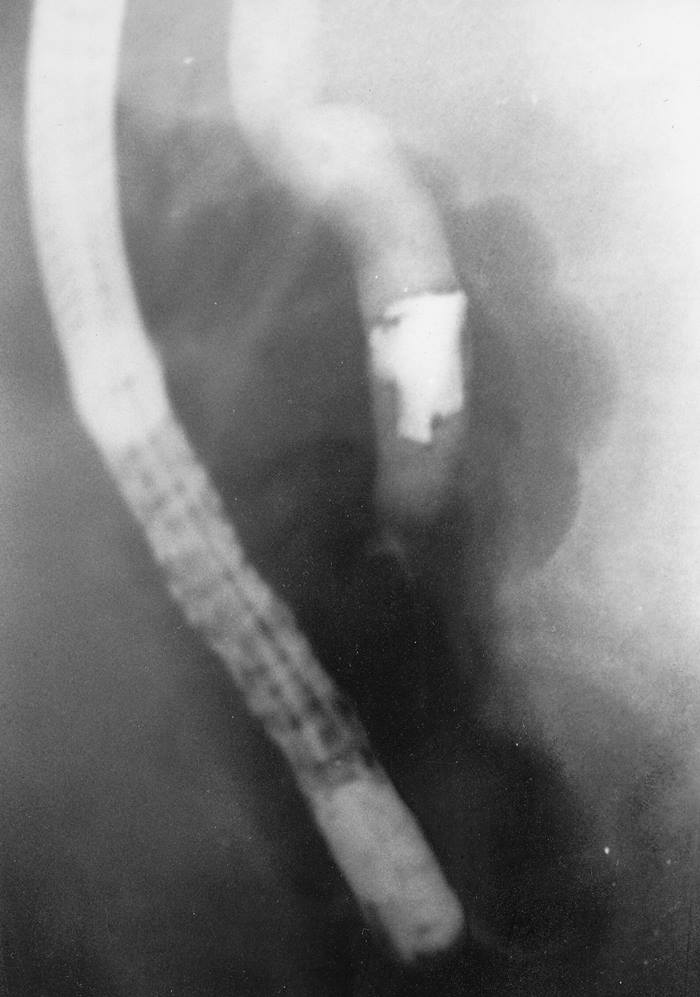

Grenade Splinter Causing Biliary Obstruction

A man born 1911 was wounded by a grenade splinter in February 1940. Almost 39 years later he was jaundiced by biliary obstruction, and a grenade splinter was found by ERCP in the distal common bile duct (image), and then surgically removed.